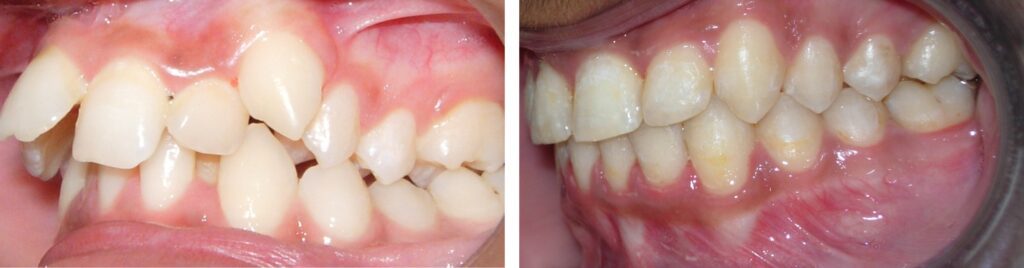

4. Đỉnh múi răng nanh quá dài

Trong trường hợp đỉnh múi răng nanh dài, tốt hơn nên gắn mắc cài về phía nướu nhiều hơn 0,5mm so với giá trị tiêu chuẩn và mài chỉnh lại đỉnh múi răng nanh khi kết thúc điều trị. Cũng có thể mài chỉnh lại đỉnh múi răng nanh trước khi bắt đầu điều trị và vẫn gắn mắc cài ở vị trí lý tưởng. Đỉnh múi răng nanh dài thường thấy ở những răng nanh bị lệch ngầm.

Độ nhô của răng nanh được giữ lại để phù hợp với tình trạng tái phát theo chiều dọc vì răng nanh ở vị trí cao trong cung răng. Để nguyên đỉnh múi răng nanh như vậy và gắn mắc cài ở vị trí bình thường sẽ để lại những vùng khớp cắn hở nhỏ ở phía trong và phía xa của răng nanh.